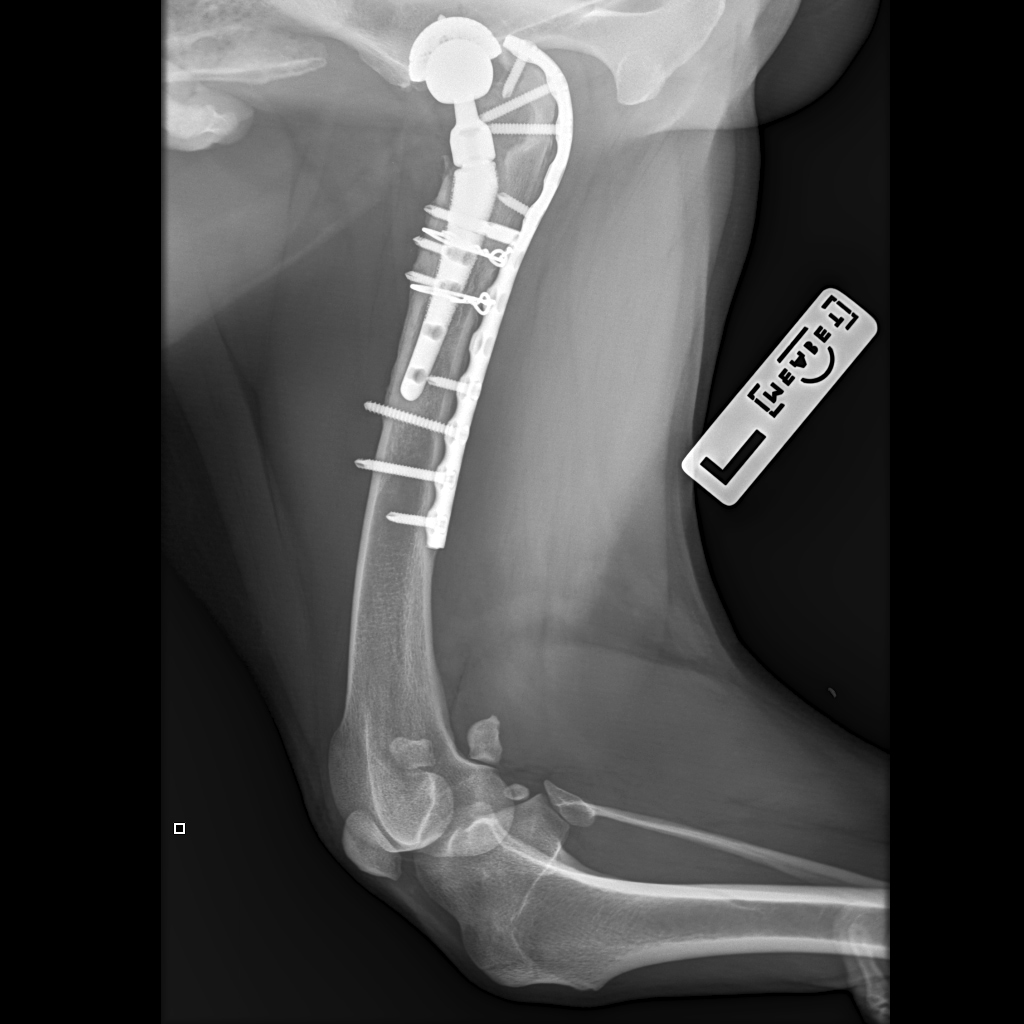

Вчера резко захромал, встал на 3 ноги и понос.

По рентгену чисто

В понедельник КТ